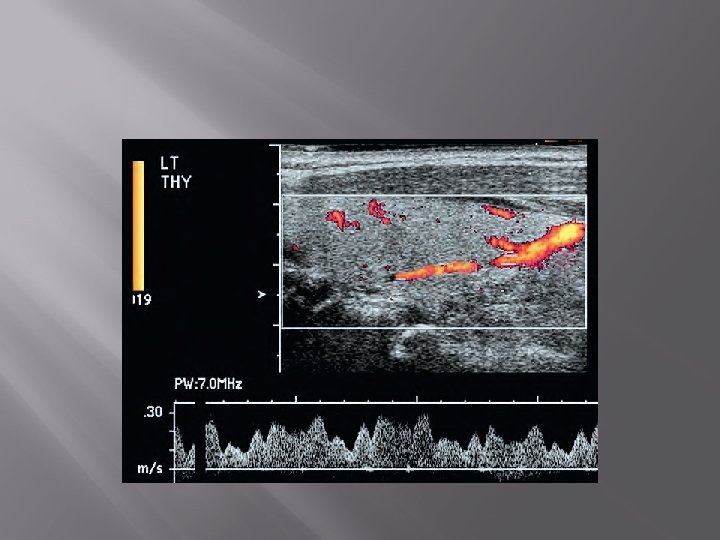

1. Ultrasonography (USG) � � Gray scale, color Doppler Transducer : linear frekuensi tinggi (7. 5 -15. 0 MHz)

Gray scale

Color Doppler